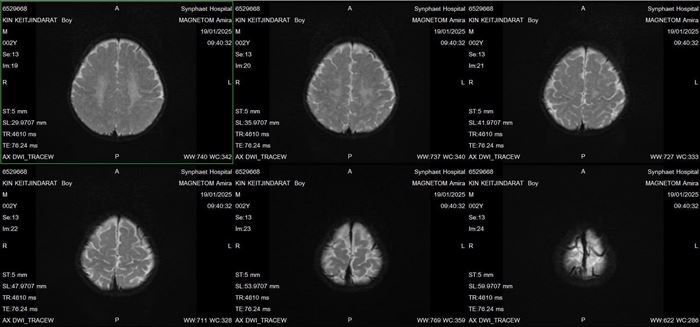

แม่พยายามหาทางพาผมไปตรวจโรงพยาบาลหลาย ๆ ที่ คุณหมอให้ตรวจเมตาบอลิก เพราะผมขับถ่ายยาก ผลก็ยังไม่มีอะไรผิดปกติ คุณหมอให้แม่ผมตรวจ MRI สมองอีกครั้ง และตรวจเลือด Genes Genetics เพื่อเป็นการตรวจหาความผิดปกติทางพันธุกรรม เพราะขาแขนผม ตึงเกร็งมากขึ้นเรื่อย ๆ แถมร่างกายของผมยังทำอะไรได้น้อยลงมาก ๆ เหมือนเด็กอายุแค่ 4-6 เดือนเท่านั้น

ผมใช้เวลาตรวจอยู่ร่วมปี พี่ ๆ อยากรู้ไหมครับ ว่าผมเป็นอะไร ผมป่วยเป็นโรค MLD ครับ เป็นโรคพันธุกรรมที่หายากมาก ๆ ชื่อว่า Metachromatic Leukodystrophy